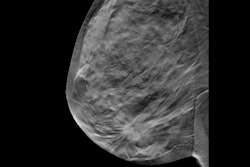

Released on May 30, the task force’s draft guidelines recommend that women between the ages of 40 and 49 should not be systematically screened. Instead, these women are advised to have informed conversations with their primary care provider and make their own screening decisions from there. Additionally, the guidelines do not recommend supplemental imaging in women with dense breasts or women with a personal family history of breast cancer.

The CTFPHC’s updated guidelines differ slightly from the guidelines issued by the U.S. Preventive Services Task Force (USPSTF) in April. The U.S. guidelines recommend biennial breast cancer screening for women ages 40 to 74, a grade B recommendation. The USPSTF also said that there was insufficient evidence to recommend supplemental screening with MRI or ultrasound in women, regardless of breast density.